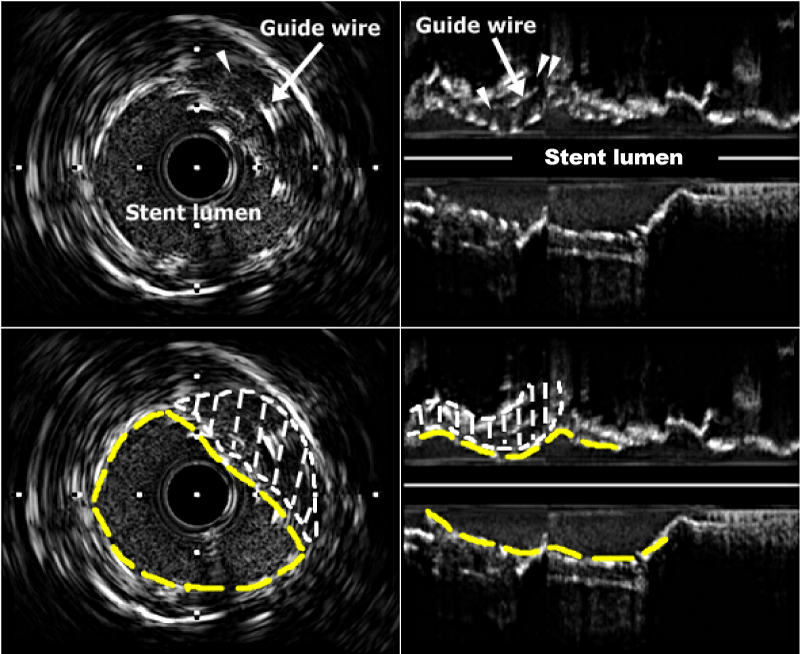

| Figure 3: IVUS images (left panel, cross-section; right panel, longitudinal section) obtained after kissing predilatation of stent and cushion balloon (refer to Fig. 1C); note the under-expanded stent and guide wire (arrow) within the expanded lumen (single arrowhead and area surround by dot, both panels), resulting from cushion balloon inflation, and the patent LCX orifice (double arrowheads, right panel). IVUS, intravascular ultrasound; LCX, left circumflex artery; Yellow dash line, stent struts. |